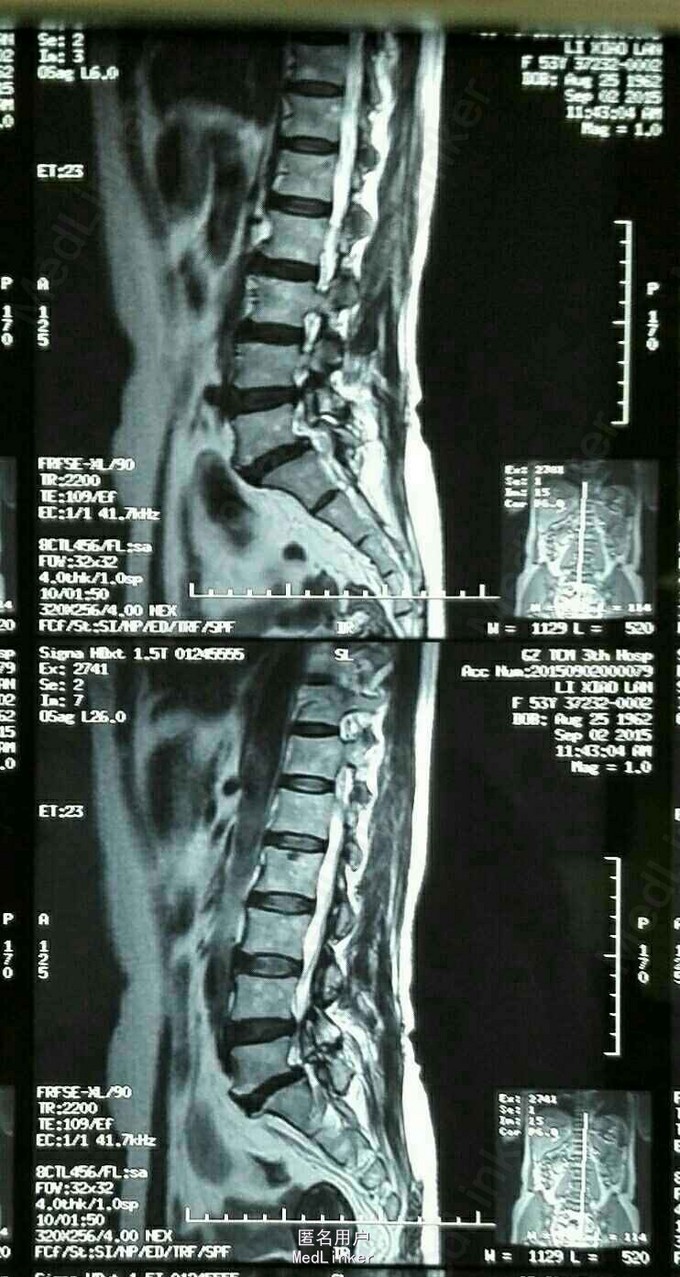

腰痛伴右下肢麻痛、乏力50余天,左下肢麻痛、乏力20天。50余天前无明显诱因出现右下肢麻痛、乏力,以麻木、乏力为主,20天前出现左下肢麻痛、乏力,行走200米时麻木加重、乏力明显,需休息后方能继续行走。经保守治疗半月,症状无明显改善,遂老我院就诊。

跛行步态,腰椎活动轻度受限,L5棘突及右侧脊旁压痛、叩痛,VAS评分腰痛3分,腿痛2分,JOA评分14分,ODI评分40%,余无明显阳性体征。外院MR提示:L5向前Ⅰ度滑脱并椎弓根峡部崩裂。我院腰椎动力位片示:1.腰椎退行性变,2. L5向前Ⅰ度滑脱并椎弓根峡部崩裂。

52岁女性患者,起病50余天,经保守治疗半月后症状无明显改善,腰椎MR及腰椎动力位片均提示:L5椎体滑脱。行L5/S1椎体融合术,术后患者双下肢麻痛及乏力明显缓解。对于腰椎滑脱的患者,经积极保守治疗后症状无明显改善者,应行手术治疗,手术效果较好。术后1月返院复查并复查腰椎X片。